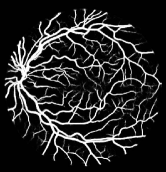

Refer to caption

Figure 1: Vessel segmentation results of side-output(s-out) layers produced by three networks. From top to bottom the network is normal DSN (with no short connections), BS-DSN (DSN with bottom-top short connections) and BTS-DSN (DSN with both bottom-top and top-bottom short connections), respectively.

As pointed out in recent works [15, 17], a good semantic segmentation network should learn multi-level features. Further, it should have multiple stages with different receptive fields to learn more inherent features from different scales. FCN, taken as an example, uses skip connections to fuse multiple stages outputs, as well as the HED network, in which a series of side-output layers are added after each stage in VGGNet. The HED network was first proposed for edge detection, and further used for image-level vessel segmentation in recent studies [6, 16], with significant performance. However, our experimental results show that such network architecture is not appropriate for vessel segmentation directly. Figure 1 provides such an illustration. Reasons for this phenomenon are straightforward. On one hand, the side-output of the first layer often contains too many noises. On the other hand, the features produced by the last side-output layer are too coarse due to information loss of pooling operation. Obviously, the inaccurate vessel map of side-output1 and side-output4 should have negative impacts on the final segmentation result.

In addition, we can observe from Figure 1 that the side-output1 and side-output4 of the BTS-DSN were more accurate compared with those of the DSN.